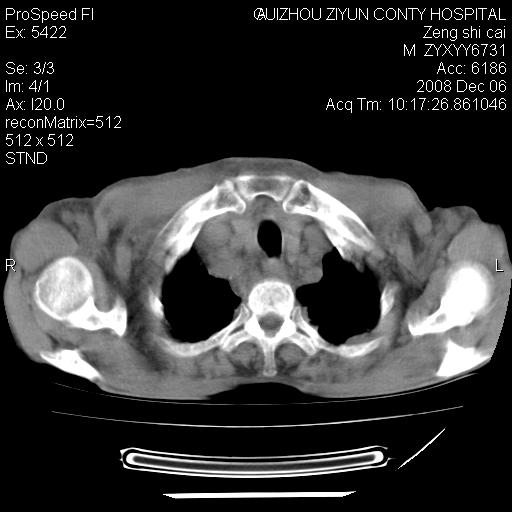

标题: CT16961:M、71岁,咳嗽半年,无血痰;胸片示右肺占位。 [打印本页]

标题: CT16961:M、71岁,咳嗽半年,无血痰;胸片示右肺占位。

右肺癌并纵隔淋巴结及胸膜转移可能性大

右肺癌并纵隔淋巴结及胸膜转移。建议气管镜

右肺纵隔型肺癌伴纵隔淋巴结及胸膜转移!

右肺纵隔型肺癌伴纵隔淋巴结转移!双侧胸水!

1)考虑右肺上叶纵隔型肺癌伴纵隔淋巴结转移。2)心包积液,双侧胸腔积液。

右肺癌并纵隔淋巴转移,腹膜后转移可能性大,两侧胸腔积液

右肺癌并纵隔淋巴结及胸膜心包转移,好多团团点点,看得有点想吐

右肺上叶纵隔型肺癌伴纵隔淋巴结转移。心包积液,双侧胸腔积液。

右上肺癌并纵隔淋巴结及胸膜转移。

右肺纵隔型肺癌伴纵隔淋巴结转移!双侧胸水\\心包积液

建议强化!主要鉴别是淋巴瘤与肺癌淋巴结转移。

右肺纵隔型肺癌伴纵隔淋巴结及胸膜转移